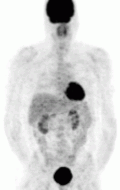

FDG PET — the tumor is appreciated as the dark structure in the patient's left chest. The darkened structure at the head of the patient is the brain, posterior to the abdomen are the kidneys, and in the pelvis is the bladder. These are normal.

Of the four above mentioned modalities, 18F-FDGPET is the most common and readily available functional imaging technique at most hospital systems, but the least-specific to neuroendocrine tumors (Image Left). In 2012, over 200 patients participated in a trial that compared the current gold standard of the time (MIBG/CT/MRI) to the novel FDG PET. Compared to its functional counterpart, FDG outperformed MIBG in detecting soft-tissue and bone metastases with higher specificity in patients with biochemically active tumors.[83]